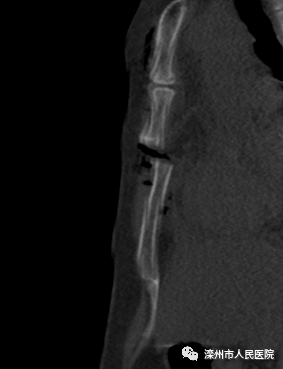

術(shù)前影像